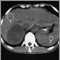

Adrenocortical carcinoma is a cancer of the adrenal glands.

Imaging tests may include: